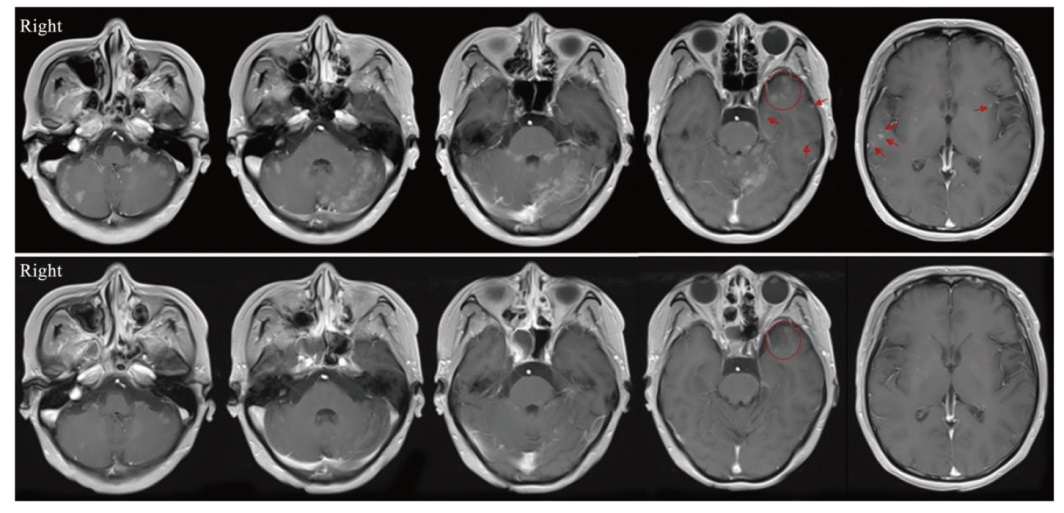

背景与目的:鞘内化疗是治疗实体瘤脑膜转移(leptomeningeal metastases,LM)的主要方法之一。既往的Ⅰ期临床研究证实了鞘内程序性死亡蛋白-1(programmed death-1,PD-1)抑制剂治疗黑色素瘤LM的安全性和潜在疗效。系统化疗联合PD-1抑制剂的协同抗肿瘤作用已被广泛认可。本研究旨在探索鞘内注射培美曲塞联合PD-1抑制剂治疗实体瘤LM的安全性及可行性。 方法:以广州医科大学附属惠州医院/惠州市第三人民医院收治的实体瘤LM患者为研究对象,采用“3+3”剂量递减策略,寻找推荐的安全给药剂量。培美曲塞给药方案为初始诱导治疗2次/周,连续2周;随后巩固治疗1次/周,连续4周;治疗有效的患者给予每个月1次维持治疗。PD-1抑制剂给药从第4次培美曲塞给药开始,每2周1次,连续6周;随后对治疗有效的患者,与培美曲塞同时给予每个月1次维持治疗。单次给药起始剂量为PD-1抑制剂(特瑞普利单抗)40 mg、培美曲塞15 mg。主要研究终点为安全性及推荐给药剂量,安全性基于不良反应进行评估。同时观察临床有效率(clinical response rate,CRR)、疾病控制率(disease control rate,DCR)和总生存期(overall survival,OS)。本研究经广州医科大学附属惠州医院/惠州市第三人民医院伦理委员会审批通过(伦理编号:2024-KY-029-01)。 结果:2024年6—9月共入组7例患者(男性3例,女性4例,中位年龄57岁),包括非小细胞肺癌6例和乳腺癌1例。所有患者的脑脊液(cerebrospinal fluid,CSF)细胞学检查结果均为阳性。6例存在LM相关神经功能障碍。5例存在LM相关影像学异常。6例完成诱导及巩固治疗并接受维持治疗。1例因细菌性脑膜炎未完成巩固期最后1次PD-1抑制剂鞘内给药,感染控制后接受维持治疗。总不良反应发生率为100%(7/7),包括骨髓抑制7例(100.00%)、转氨酶升高3例(42.86%)、乏力2例(28.57%)和甲状腺功能减退1例(14.29%)。其中3级不良反应发生率为42.86%(3/7),全部为骨髓抑制。免疫相关不良反应(immune-related adverse event,irAE)发生率为14.29%(1/7),为Ⅱ级甲状腺功能减退。未见剂量限制毒性(dose-limiting toxicity,DLT)发生,推荐剂量为PD-1抑制剂40 mg联合培美曲塞15 mg。3例患者神经功能改善,1例CSF细胞学检查结果转阴,2例影像学缓解。根据神经肿瘤疗效评估(response assessment in neuro-oncology,RANO)标准,CRR为57.14%(4/7),DCR为100%(7/7)。3例出现远隔效应,分别表现为脑转移灶、原发肺病灶及纵隔淋巴结缩退。截至2025年4月10日,1例死亡,中位随访时间为7.7(5.9~9.3)个月。中位OS未达到。6个月OS率为85.71%。 结论:鞘内注射培美曲塞联合PD-1抑制剂治疗非小细胞肺癌等实体瘤LM患者显示出良好的安全性和可行性,并且具有潜在的临床疗效。

Background and purpose: Intrathecal chemotherapy is one of the mainstay treatment options for leptomeningeal metastases (LM) from solid tumors. A previous phase Ⅰ study demonstrated the safety and potential efficacy of intrathecal anti-programmed death receptor 1 (anti-PD-1) for LM from melanoma. The synergistic efficacy of systemic chemotherapy combined with anti-PD-1 has been widely known. This study aimed to evaluate the safety and feasibility of intrathecal chemotherapy (pemetrexed) and anti-PD-1 (toripalimab) for LM patients from solid tumors. Methods: The subjects were patients with LM from solid tumors who were treated at Affiliated Huizhou Hospital of Guangzhou Medical University/Third People’s Hospital of Huizhou City. A 3+3 dose de-escalation strategy was implemented to determine the recommended dose with an initial dose of PD-1 inhibitor (toripalimab) 40 mg and pemetrexed 15 mg. Pemetrexed was administered twice weekly for the initial 2 weeks of induction therapy, once weekly for the subsequent 4 weeks of consolidation therapy, and once monthly during maintenance therapy. PD-1 inhibitor was initiated at the 4th administration of pemetrexed, administered every 2 weeks for 6 weeks; subsequently, responders continued monthly maintenance therapy alongside pemetrexed. The primary objective was to assess safety based on adverse events and the recommended dose. All participants were observed to investigate the clinical response rate (CRR), disease control rate (DCR) and overall survival (OS). This study was approved by the ethics committee of Affiliated Huizhou Hospital of Guangzhou Medical University/Third People’s Hospital of Huizhou City (ethics number: 2024-KY-029-01). Results: Seven patients (male: 3, female: 4, median age: 57 years) were enrolled between June and September 2024, including non-small cell lung cancer (6) and breast cancer (1). All patients presented with positive cerebrospinal fluid (CSF) cytology. Six patients presented LM-related neurological dysfunction. Five patients showed LM-related neuroimaging findings. Six patients completed the induction and consolidation therapy, and subsequently received maintenance therapy. One patient, due to bacterial meningitis, did not complete the final administration of toripalimab during consolidation therapy, and maintenance therapy was administered after infection control. Adverse events rate was 100% (7/7), including myelosuppression (100.00%, n=7), elevation of hepatic aminotransferases (42.86%, n=3), fatigue (28.57%, n=2) and hypothyroidism (14.29%, n=1). Three (42.86%) patients had grade 3 adverse events (myelosuppression). The immune-related adverse event (irAE) rate was 14.29%, manifested as hypothyroidism (Grade 2). No dose-limiting toxicity (DLT) was observed. Thus, no de-escalation was applied. The recommended dose was determined to be PD-1 inhibitor 40 mg in combination with pemetrexed 15 mg. Three patients showed improved neurological dysfunction, 1 with CSF cytological response, and 2 with neuroimaging improvement. CRR was 57.14% (4/7) by response assessment in neuro-oncology (RANO) proposal criteria. DCR was 100% (7/7). Three patients exhibited abscopal effects with regression of brain metastasis lesions, primary lung lesion and mediastinal lymph nodes, respectively. As of April 10, 2025, 1 patient died. The median follow-up time was 7.7 (5.9-9.3) months. The median OS was not reached with a 6-month OS rate of 85.71%. Conclusion: The combination therapy of intrathecal pemetrexed and a PD-1 inhibitor was well-tolerated and feasible, while also exhibiting potential clinical efficacy in treating LM from solid tumors including non-small cell lung cancer.